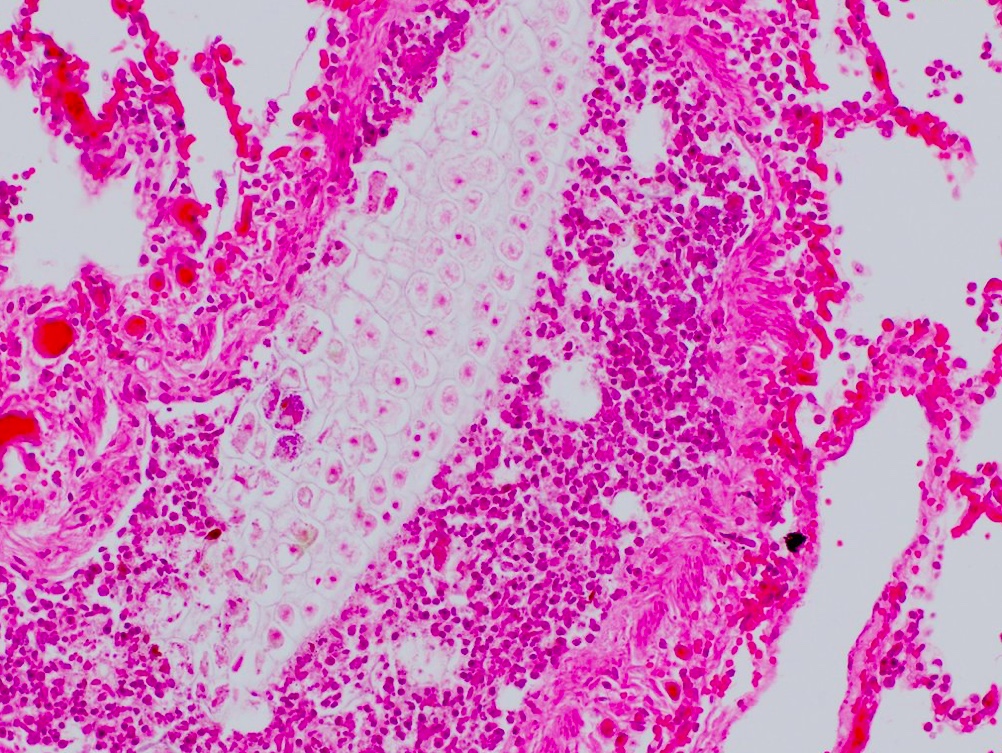

For medical students: what is the histologic abnormality (just describe what you see-I don't expect you to necessarily know the specific name/disease association)

For pathology residents: what is the likely disease association(s)?